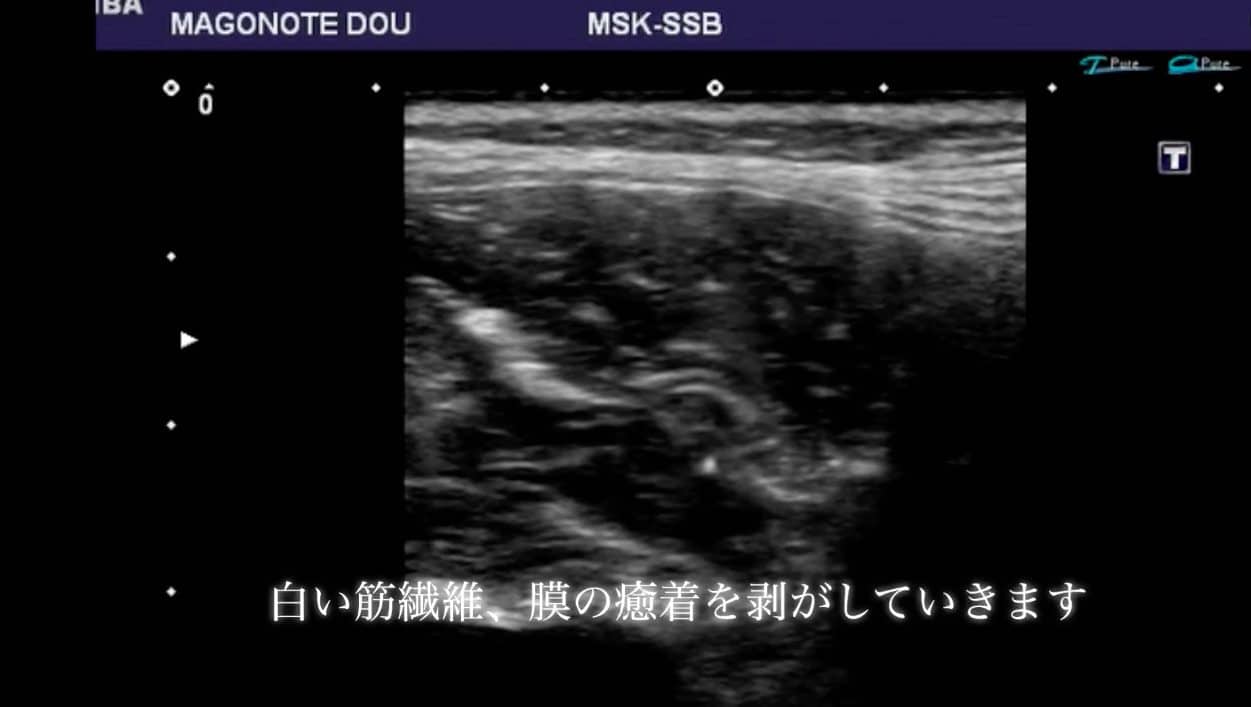

超音波エコーにて原因となる部位を観察します。

今回観察している部位は腰の筋肉内です。

痛みやしびれの原因となる部位、筋肉内の悪くなっているところは超音波エコー観察時ににて【白く】映し出されることが多いです。

その悪くなっている白い部位(筋膜の癒着部位)に鍼(はり)を刺して、くっついてしまっている部位を剥がし、痛みや痺れの改善に大きく繋げていきます。